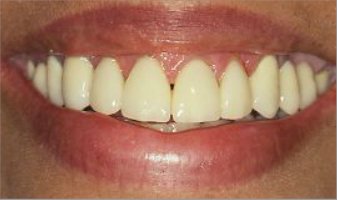

Rehabilitación completa, fundas de porcelana y tratamiento periodontal